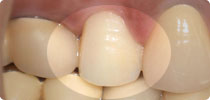

歯の抜けたところにチタン製の人工歯根を埋め込み、人工の歯を被せます。入れ歯のように金属製の留め具(バネ)がなく、ブリッジのように隣の歯を削る必要もないため、見た目が自然であるだけでなく、残っている歯に負担をかけません。また骨としっかり固定されているので、自分の歯のように噛むことができます。入れ歯にご不満のある方は、お気軽にご相談ください。

- インプラントによるしっかりした土台ができたら、人工の歯を上に取り付けます。